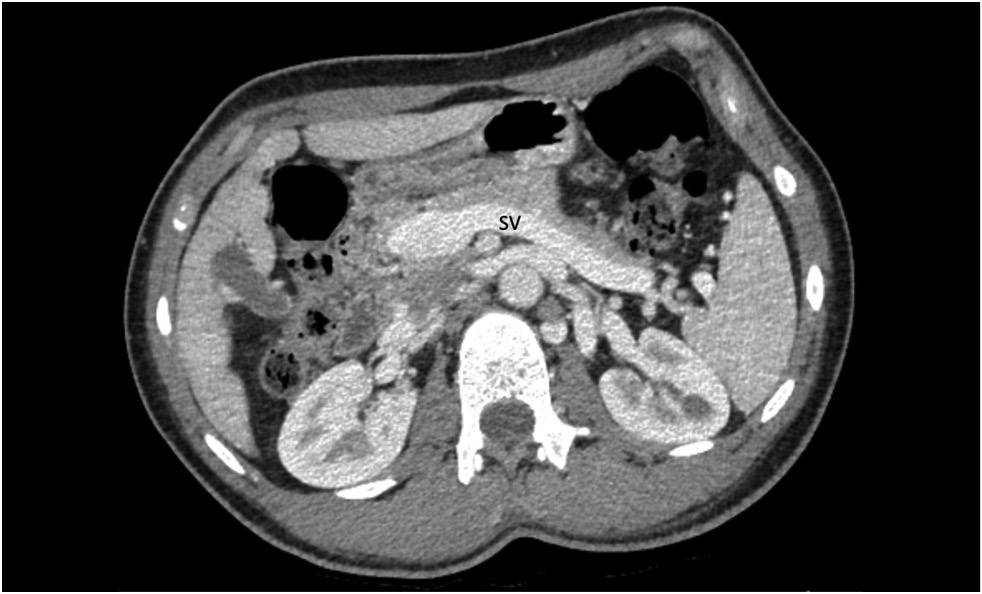

В статье описан клинический случай мальформации Абернети типа Ib у 15-летнего пациента с длительным анамнезом повышенного артериального давления, рецидивирующими носовыми кровотечениями, болью в груди, головокружением, одышкой, низкой толерантностью к физической нагрузке, эпизодами крови в стуле, болью в эпигастральной области, тошнотой и зудом. В результате проведённого комплексного обследования у пациента была диагностирована аномалия развития портальной системы: расширенный кондуит воротной вены, впадающий непосредственно в нижнюю полую вену. Выявлены также множественные узлы в паренхиме печени, расширение камер сердца, гипертрофия миокарда и лёгочная гипертензия. Учитывая выраженность симптомов, размеры и тип шунта, междисциплинарным консилиумом рекомендована трансплантация печени.